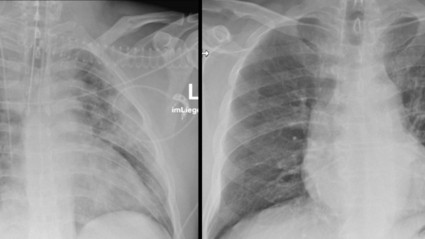

Seit Beginn der Corona-Pandemie werden Bildgebungsverfahren – wie Röntgen- oder CT-Aufnahmen – für die Diagnose von SARS-CoV-2 genutzt. Mithilfe radiologischer Bildgebung kann eine Corona-Infektion sicher erkannt und bewertet werden.

Im Fokus eigener Forschungsprojekte im RACOON Netzwerk steht am Universitätsklinikum Ulm die Entwicklung und klinische Überprüfung KI-basierter Prädiktionsmodelle für den klinischen Verlauf einer COVID-19 Erkrankung. „Auf dem Röntgenbild wie dem CT-Bild wird die Infektion sichtbar. Im CT-Bild zeigen sich typischerweise sogenannte milchglasartige Veränderung beider Lungenflügel“, erklärt Professor Meinrad Beer, Ärztlicher Direktor der Klinik für Diagnostische und Interventionelle Radiologie am Universitätsklinikum Ulm. „Die KI wird nun so trainiert, dass sie erkennt wie schwer die Infektion ist und welcher Teil der Lunge befallen ist. Die hierdurch gewonnenen Erkenntnisse stellen einen wichtigen Beitrag zur Optimierung der Therapie von Covid-19-Patient*innen dar“, ergänzt der Radiologe.